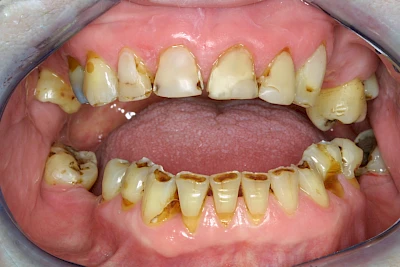

Auswaschung

Auswaschung (Erosion) dagegen ist eine Verschleißerscheinung der Zähne aufgrund von immer wiederkehrenden Säureangriffen durch die Nahrung, verstärkt zum Beispiel durch den Genuss säurehaltiger Getränke oder Speisen. Auch bei Menschen mit einer Essstörung (z. B. Bulimie) können die Zähne durch die Magensäure ausgewaschen erscheinen.